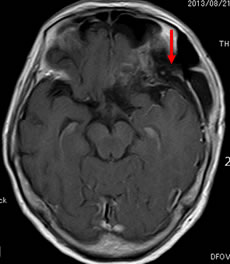

当院での症例をお示しします。症例は66才女性、進行する左眼の視力(左:手動弁)、視野障害にて当院来院。MRIにて赤矢印のように左蝶形骨内側に大きな腫瘍を認めます。開頭手術治療前に腫瘍の栄養血管にカテーテルを入れて、固体塞栓物質を造影剤と混ぜて注入します。最後に再開通しない様プラチナコイルを留置して終了します。その2日後に腫瘍摘出を行いましたが、出血は少量で輸血も行っておりません。視力も左は1.5まで改善し、患者さんは元気で退院しました。(図1-a・b、図2-a・b、図3-a・b、図4-a・b)

図2-a:術前 |

図2-b:術後 |